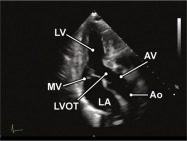

| 2.3. Mặt cắt trục dài cạnh ức phóng đại van động mạch chủ

Cửa sổ siêu âm cạnh ức

Mặt cắt trục dài cạnh ức Đặt hộp phóng đại vào vị trí van động mạch chủ, đường ra thất trái, động mạch chủ lên Chùm siêu âm đặt vuông góc với cấu trúc và có thể đặt đầu dò lên các khoang liên sườn cao hơn nếu cần. |

Van động mạch chủ (AV) | |||||